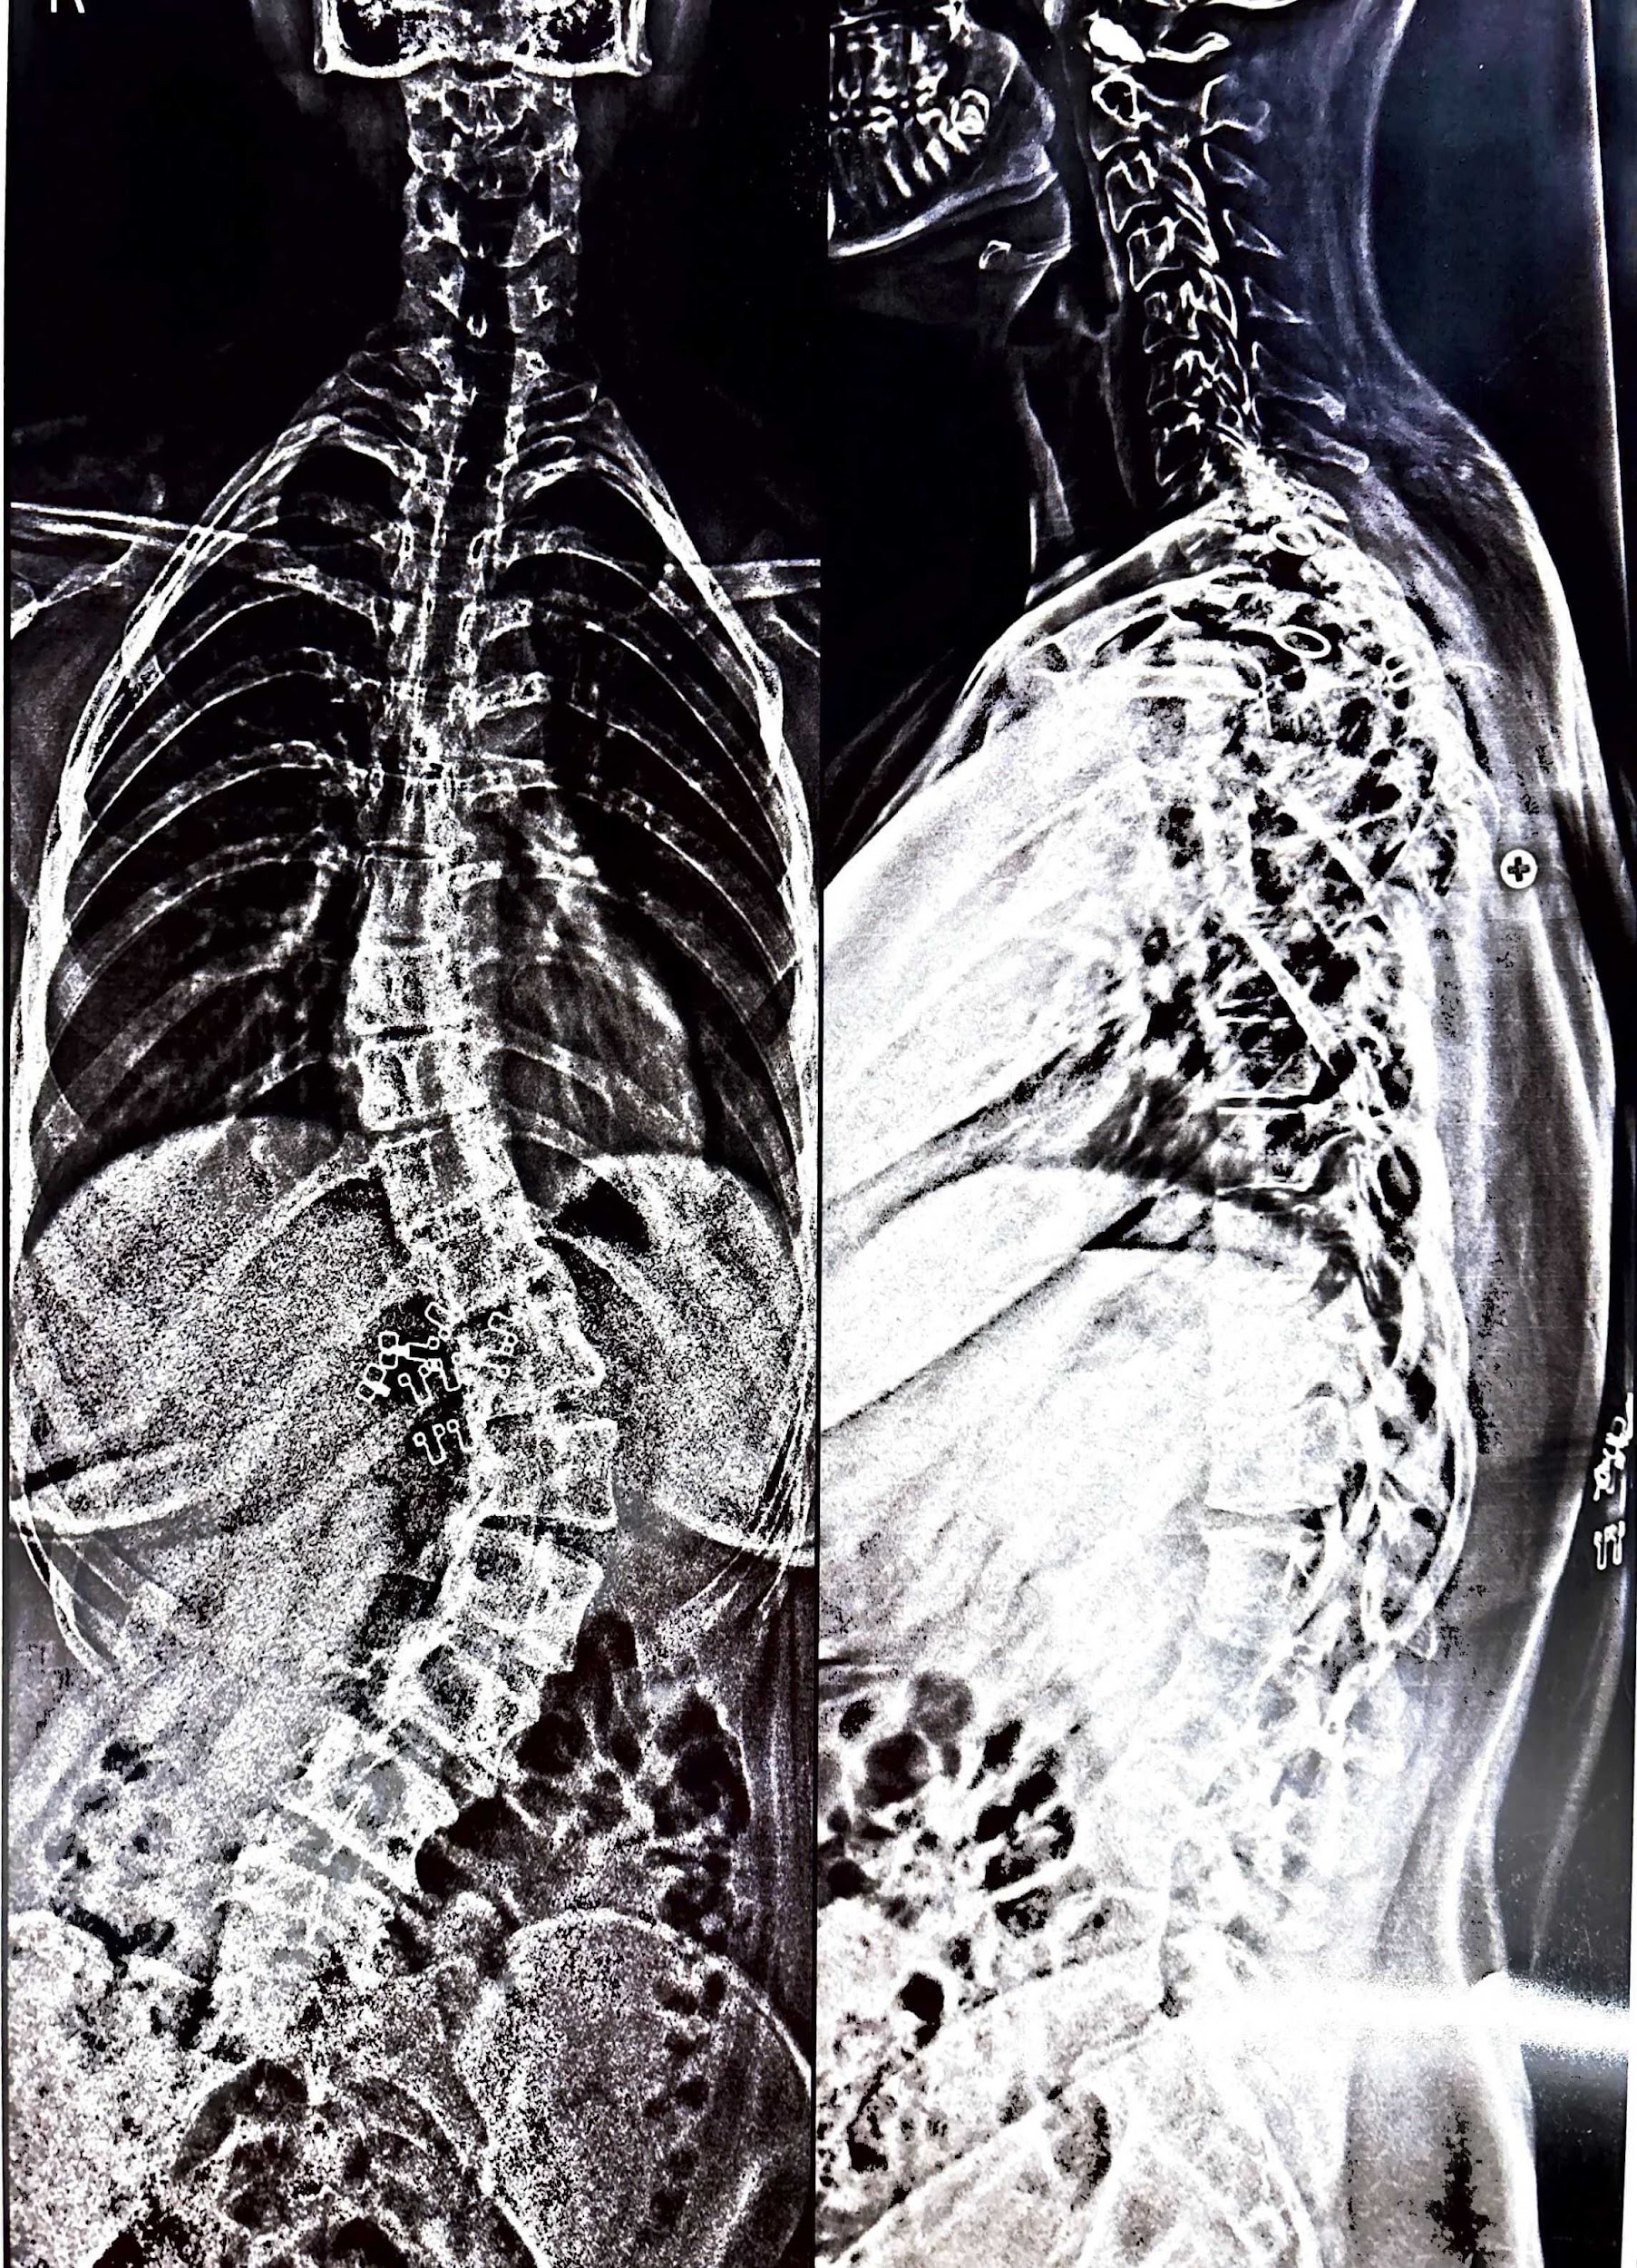

Learn how orthopedic surgery is enhanced with blood conservation techniques. Learn how to reduce blood...

Orthopedic surgery corrects joint, muscle, ligament, and bone problems. The most frequent motives for undergoing...

A fracture is simply a broken bone. It may be due to when one stumbles,...

A bone fracture is when a bone in your body cracks or breaks. It may...